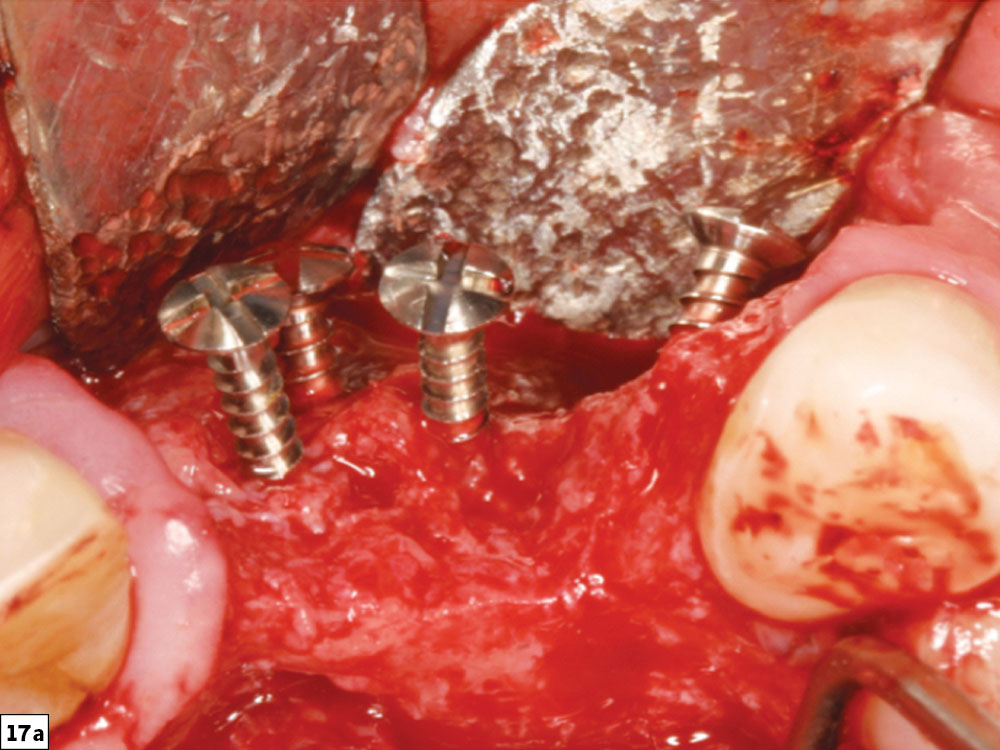

To obtain optimal function and esthetics in implant dentistry, the hard and soft tissues need to be present in adequate volume and quality. The guided bone regeneration technique has been shown to be very successful and predictable in augmenting these tissues. The correction of alveolar bony ridge deficiencies, once thought to be difficult or impossible, should be in every clinician’s procedural arsenal (Figs. 16a–16e). However, these procedures are technique-sensitive, and therefore all procedural steps must be strictly followed. In this article, a GBR ridge augmentation protocol has been discussed in eight procedural steps that allow for predictable bone grafting (Figs. 17a–19b).

Concavity-type defect

post-healing image depicting bone growth to the level of the tenting screws

Figures 17a, 17b: Concavity-type defect (17a) and final post-healing image depicting bone growth to the level of the tenting screws (17b).